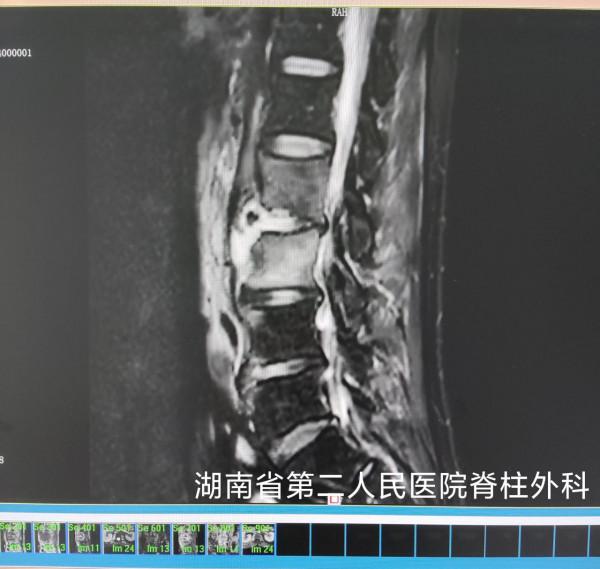

脊柱外科主任何飛平主任醫師及蓋景穎副主任醫師接診,詳細檢查、分析、查因,經抗結核、抗非特異性感染藥物及臥床休息等保守治療後效果不佳,經評估最終決定採取手術治療,並予置管沖洗引流。術後標本培養結果顯示,竟是白色念珠菌感染!

王大叔最終被診斷為:腰椎椎間隙感染(真菌性脊柱炎,白色念珠菌),蓋景穎醫生立即調整治療用藥,並結合沖洗,經過近兩個月的治療,王大叔的症狀逐漸緩解,恢復良好後出院。王大叔終於擺脫了病痛的折磨,對醫護團隊十分感激。

真菌性脊柱炎的診斷除根據臨床症狀、體徵及影像學表現外,主要依據病變標本中(或分泌物內)分離、培養出致病真菌,或依據病理切片進行確診。